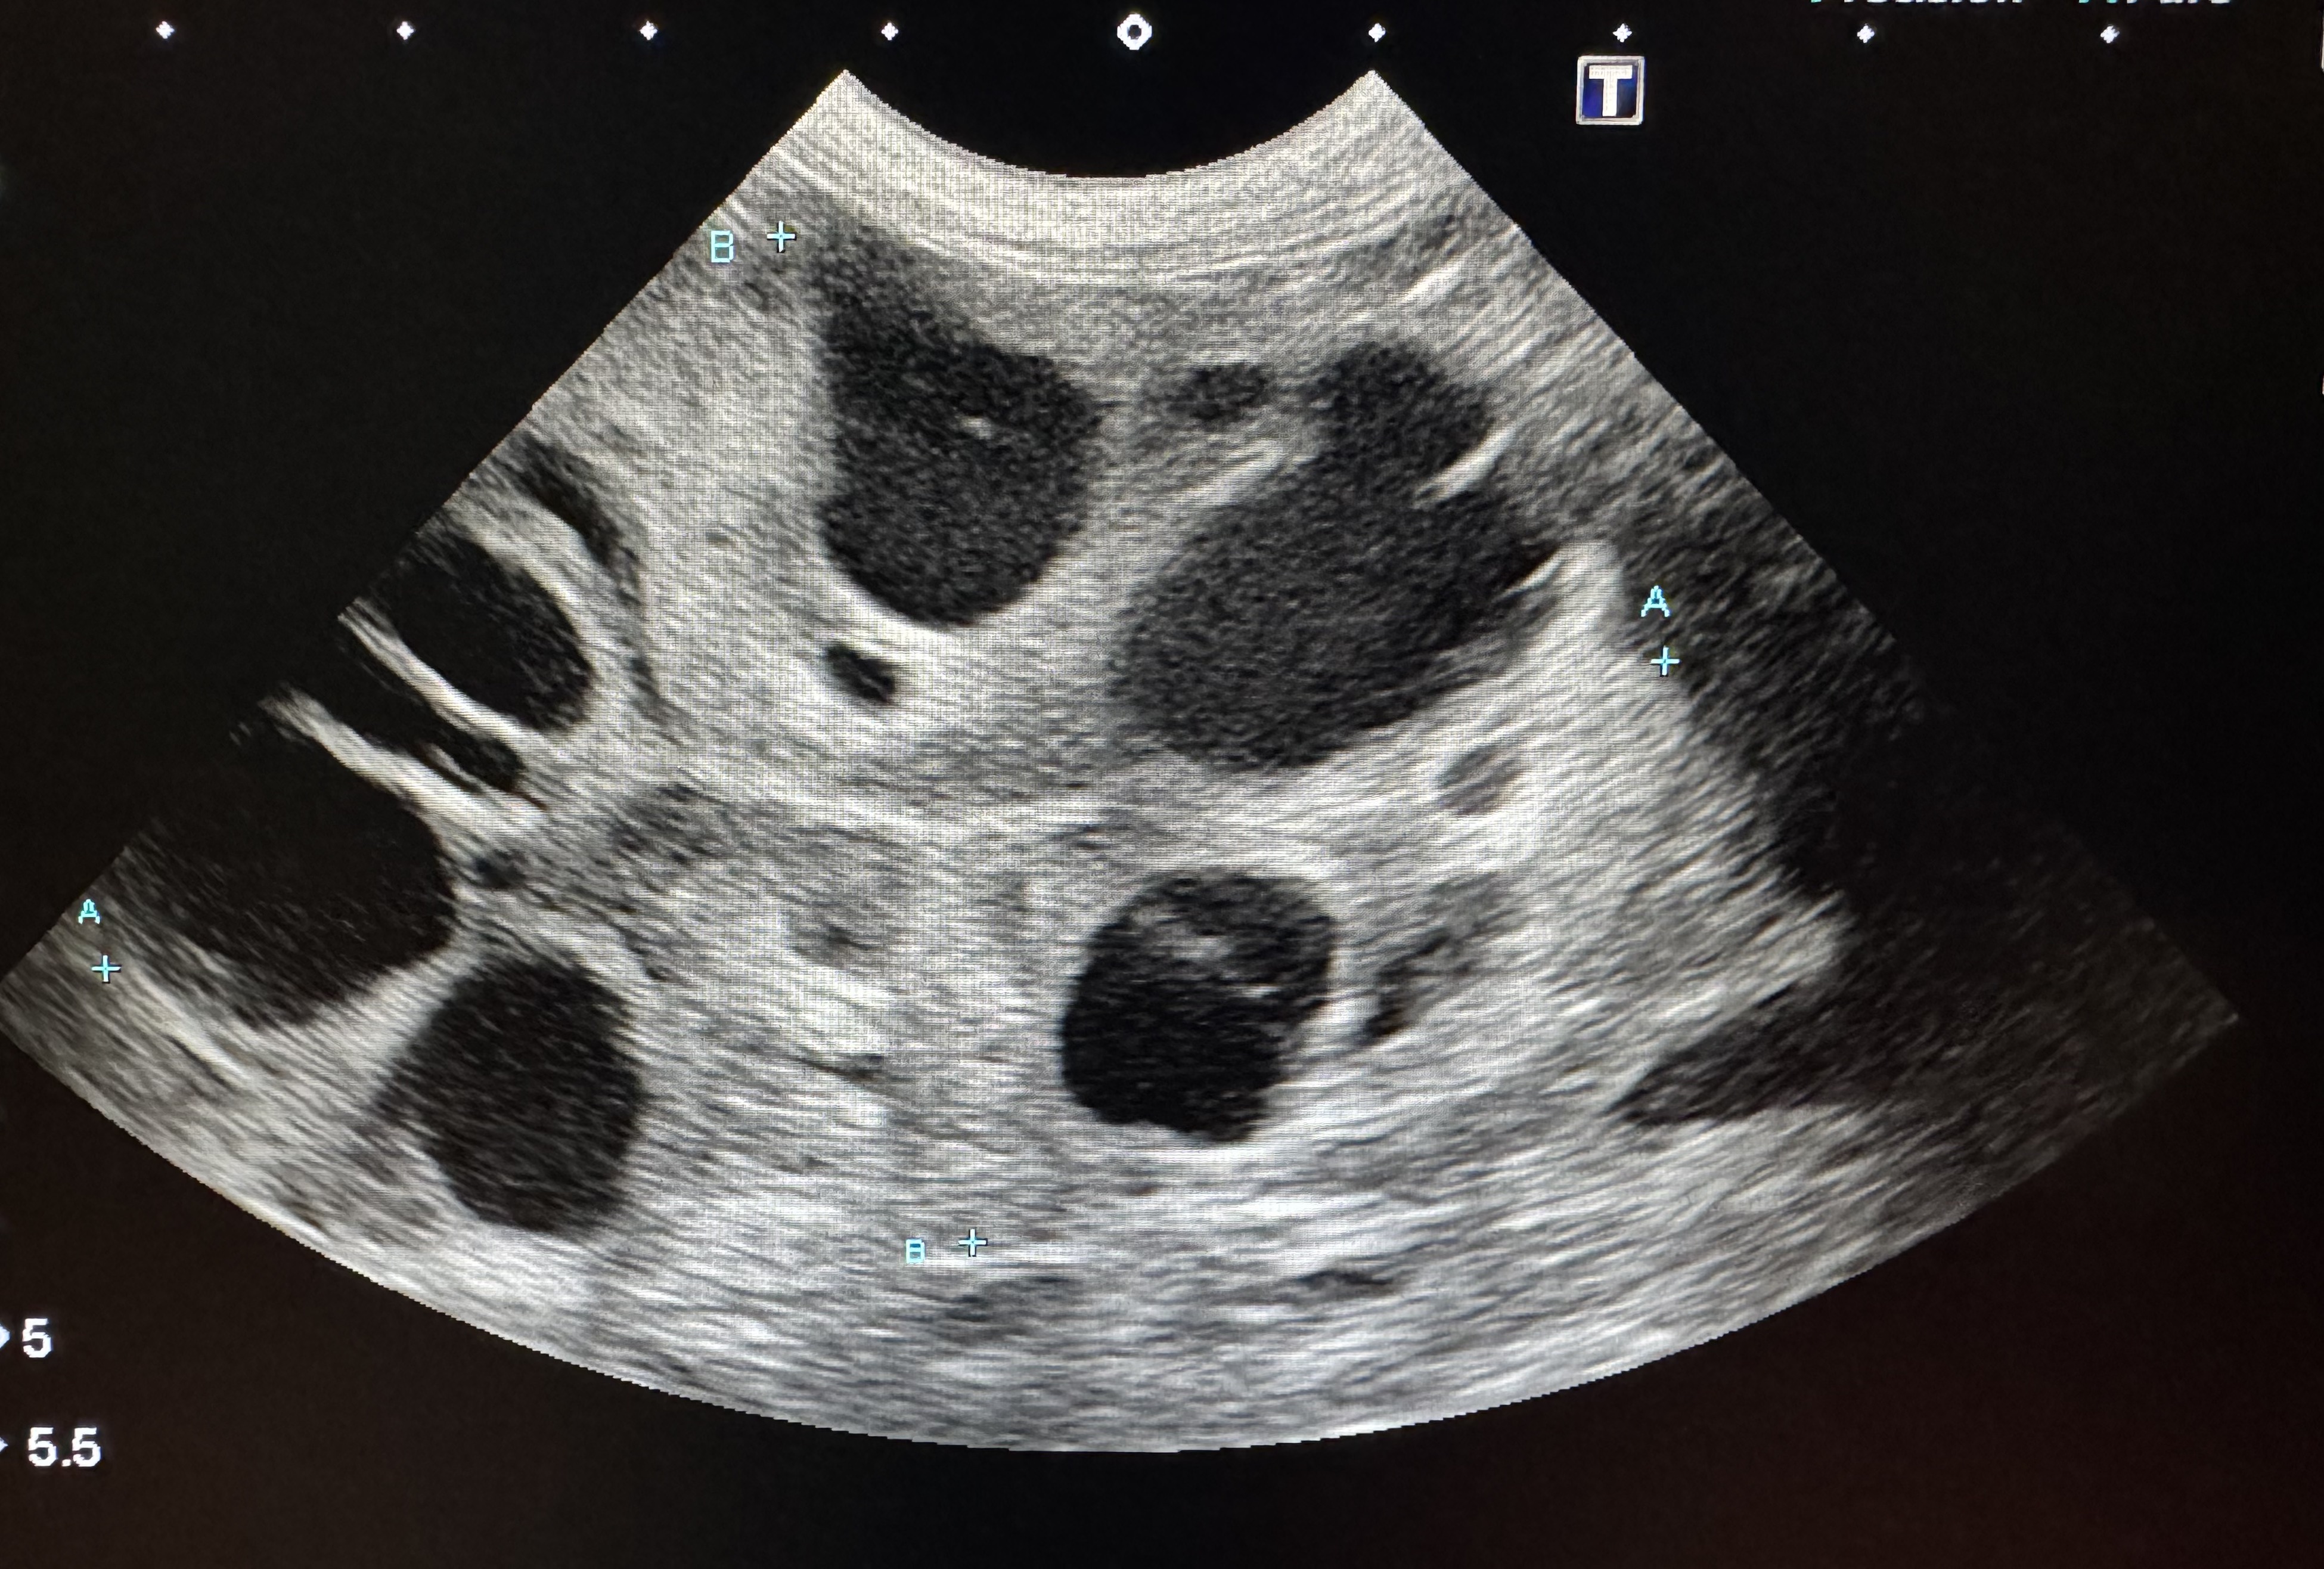

慢性腎不全の猫で多発嚢胞状の変化を引き起こしてしまった腎臓のエコーの写真です。原因を明らかにしてから治療することで、慢性腎不全の高齢の猫でも苦痛や病気の進行を最小限に、質を高めた生活を送ることもできますので、気軽にご相談ください。